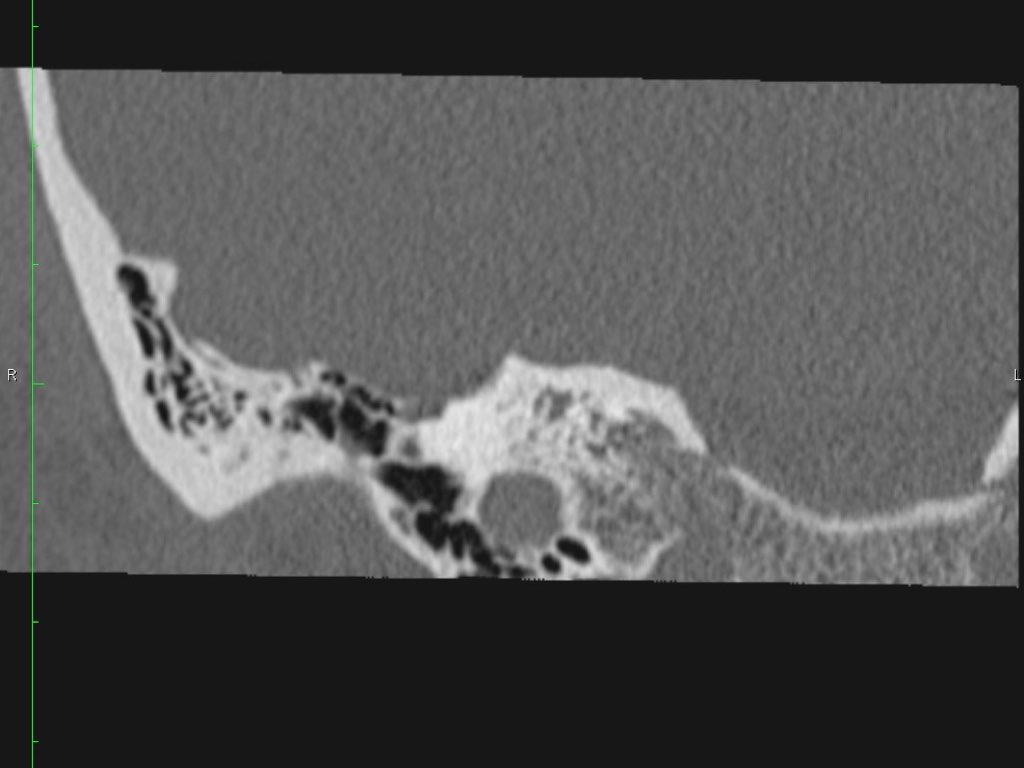

Đoạn mê nhĩ của dây thần kinh mặt xuất phát từ ống tai trong, chạy gần như vuông góc với trục dài của xương đá, gập góc nhọn về phía trước để đến hạch gối (geniculate ganglion).

Tại hạch gối, dây thần kinh mặt tạo thành một khúc quặt hình chữ U (genu thứ nhất của dây thần kinh mặt) để chạy ra phía sau theo đoạn nhĩ dọc theo thành trong của thượng nhĩ.